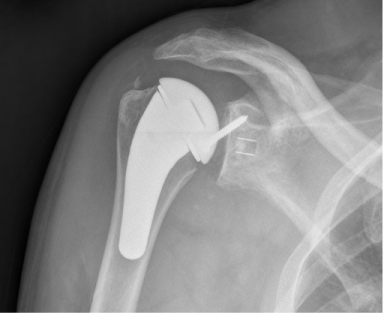

Anatomic Shoulder Replacement